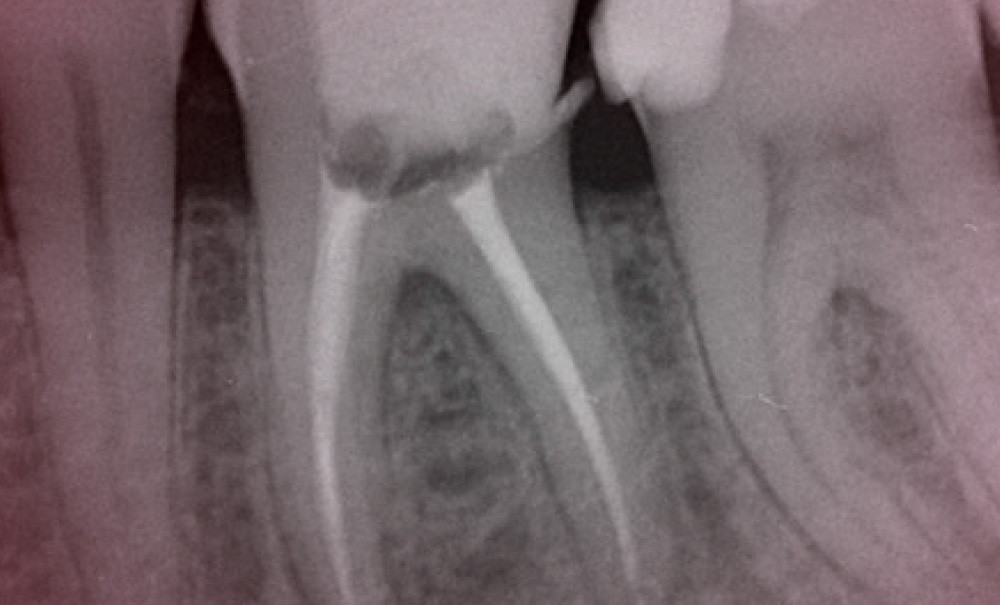

L’obturation canalaire est la dernière étape du traitement canalaire. Elle est réalisée après la mise en forme et la désinfection. Elle est souvent considérée comme compliquée à mettre en œuvre et est responsable des plus grandes frustrations. La raison est qu’elle est finalement la seule partie objective du traitement mené jusqu’ici en partie à l’aveugle, et que la radiographie postopératoire est la seule chose « que l’on voit ». Si l’image radiographique est décevante, l’échec ressenti est immédiatement assimilé à la technique d’obturation choisie et à sa mise en œuvre.

Pourtant, la qualité de l’obturation est directement reliée au succès des étapes précédentes répondant à la trilogie décrite par Schilder [1] sur l’intime relation qui existe entre mise en forme, désinfection et obturation. Un canal non préparé ne peut être ni désinfecté, ni obturé correctement. Nous pourrions rapprocher ce concept de celui des obturations coronaires à…